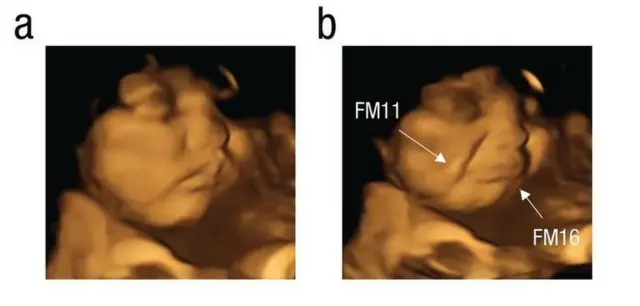

ኣብ ማህጸን ዝርከቡ ዕሸላት፡ ኣደታቶም ካሮት ክበልዓ ከለዋ ‘ፍሽኽ ከምዝብሉ’፡ ሓምሊ ክምገባ ከለዋ ድማ ‘ጽውግ ከምዝብሉ' ኣብ ብሪጣንያ ኣብ 100 ነፍሰጾራትን ዕሸላትን ዝተገብረ ሓድሽ መጽናዕቲ ኣረጋጊጹ።

እቲ ጕጅለ ኣብ መጽሄት ሳይኮሎጂካል ሳይንስ ዘውፅኦ ሓበሬታ ከምዘመልክቶ፡ እተን ኣደታት ነቶም ‘ካፕሱላት’ ካብ ዝውሕጣ ድሕሪ 20 ደቓይቕ፡ ብ4D ኣልትራሳውንድ ክረኣያ እንከለዋ መብዛሕትኦም እቶም ንሓምሊ ዝተቓልዑ ዕሸላት ተጸዊጐም ክብሉ እንከለዉ፣ እቶም ንካሮት ዝተቓልዑ ከኣ ፍሽኽታ ዝመልኦም ነይሮም።

ኣብ ዕሸላት እተን ካብ ክልቲኡ ዘይተወሃበን 30 ነፍሰጾራት ግን ዝዀነ ምላሽ ኣይተራእየን።

ኣብቲ ብኣልትራሳውንድ ዝረአ ጽዋገን ፍሽኽታን "እቲ ንመሪር መኣዛ ምላሽ ዝህብ ዘሎ ምንቅስቓስ ጭዋዳታት ክኸውን ይኽእል'ዩ" ክትብል ተረድእ - ራይስላንድ።